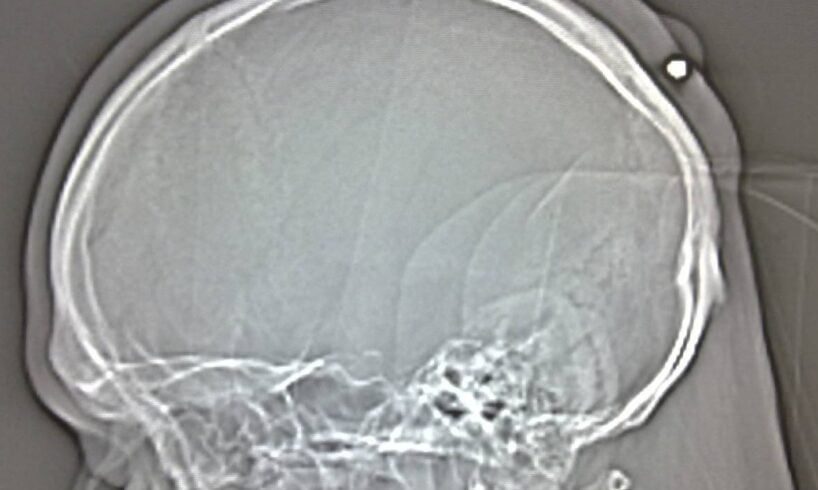

Ai sanitari ha detto di essere caduto e di accusare un forte mal di testa. Le sue condizioni, però, sono rapidamente peggiorate e la Tac a cui è stato sottoposto ha rivelato la presenza di un piccolo proiettile, forse esploso da una pistola ad aria compressa. Il giovane è stato trasferito all’ospedale Sant’Elia di Caltanissetta per essere sottoposto a un intervento chirurgico necessario ad estrarre il proiettile.

I medici del reparto di Neurochirurgia dell’ospedale Sant’Elia di Caltanissetta, che stanno tenendo sotto costante osservazione il sedicenne di Licata, non confermano, ma neanche smentiscono, che il giovane abbia un proiettile in testa.

A parlare di proiettile di circa 7 millimetri, nella testa dell’adolescente, erano stati i medici dell’ospedale San Giacomo d’Altopasso che hanno disposto appunto il trasferimento a Caltanissetta. Il minorenne di Licata ha, invece, sempre sostenuto d’essere caduto e d’aver battuto la tempia. Delle indagini si sta occupando la polizia.